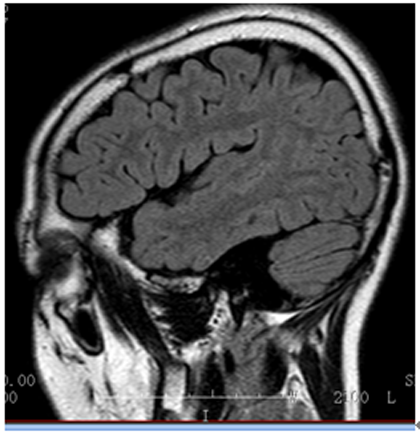

入院诊断:癫痫。入院后完善相关检查,VEEG:发作期:眨眼→左侧面肌、上肢强直→左侧偏转→BAST(左)→GTCS。MRI:右侧眶额回灰白质分界不清,弥漫性脑萎缩。PET:右侧额极及内侧面低代谢,右侧眶额回稍低代谢,右侧岛叶代谢减低。韦氏智力:全量表83,言语78,操作91;记忆63。染色体结果:47,XXY。

▲ 3T2FLAIR矢状位